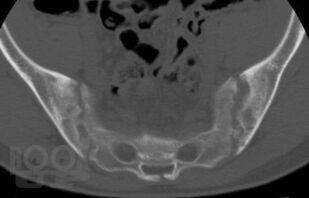

В учебном пособии представлены основные сведения о ревматологических заболеваниях, которые протекают с поражением суставов кисти, подробно изложена их рентгенологическая семиотика, описаны диагностические возможности других методов лучевой диагностики, таких как ультразвуковая диагностика, магнитно-резонансная и компьютерная томография. Особое внимание уделено дифференциальной диагностике заболеваний кисти.